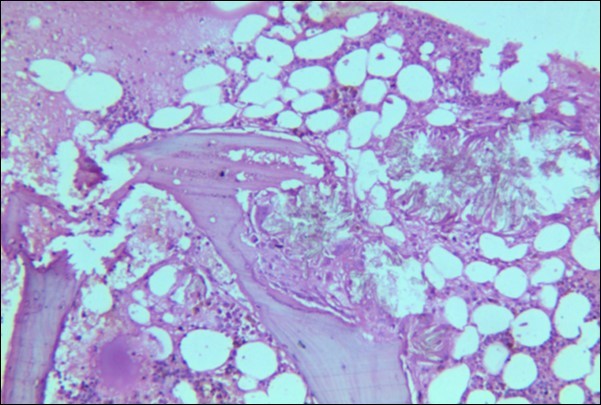

A 30 years old male, resident of Lahore was admitted for opinion regarding the necessity for regular hemodialysis after rejection of second renal transplant. Family history was suggestive of hereditary disease as two of his sisters had died of nephrocalcinosis leading to chronic renal failure at the age of 4 years. Consanguineous marriages in past many generations were also reported. Three cousins of the patient had recurrent stones with normal kidney functions. His past history revealed retention of urine at the age of 5 years due to stone in urethra. Patient presented again after 20 years in 2008 with retention of urine which was relieved by catheterization. Renal ultrasound and X ray KUB reported normal kidneys in both instances. Work up for stone formation was not undertaken at that time. The patient was put on hemodialysis and was planned for transplant which was undertaken in May 2009. After one month, follow up tests revealed Serum Creatinine to be 2.0 mg/dL. Renal Biopsy done in Sep 2009 revealed rejection of transplant. Hemodialysis was started and a second transplant was contemplated. Hemodialysis continued for 2 years till Dec 2011 when second transplant was carried out. A repeat renal biopsy was indicated for increasing serum creatinine. Again transplant rejection was evident on histology. Further investigations revealed Urinary oxalate excretion exceeding 40 mg/day (30 mg Oxalate/gram creatinine). His Blood investigations at the time bone marrow studies revealed bicytopenia with a Haemoglobin of 7.8g/dl, White blood cell count of 5.8 x 109/l; Platelet count of 120 x 109/l. Serum Creatinine was 3.6mg/dl. An attempt to correct the cytopenias by iron, vitamin B12 and folic acid supplements met with failure. No response to anemia could be elicited by adding erythropoietin to the treatment regimen. Renal and bone marrow biopsy were undertaken. Renal biopsy of the patient revealed crystals of calcium oxalate in the tubules (Figure 1). The same crystals were also visualized in bone marrow aspirate (Figure 2a and Figure 2b) and trephine biopsy (Figure 3).

Figure 3.Photomicrograph of bone marrow core from case 1 showing radially arranged calcium oxalate crystals replacing haemopoietic tissue with invasion and destruction of bony trabeculae. Areas of necrosis and a cluster of hemosiderin laden macrophages is visible.